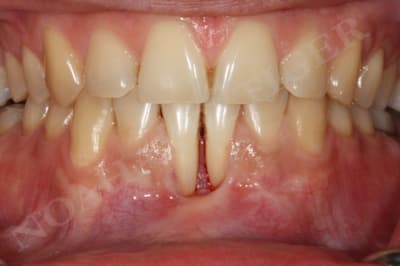

Initial ctkv65 - Eugenol

Dans le cas suivant, l'atteinte interproximale 31-41 n'autorise malheureusement aucune solution de recouvrement radiculaire :

Img 8511 llqbsh - Eugenol